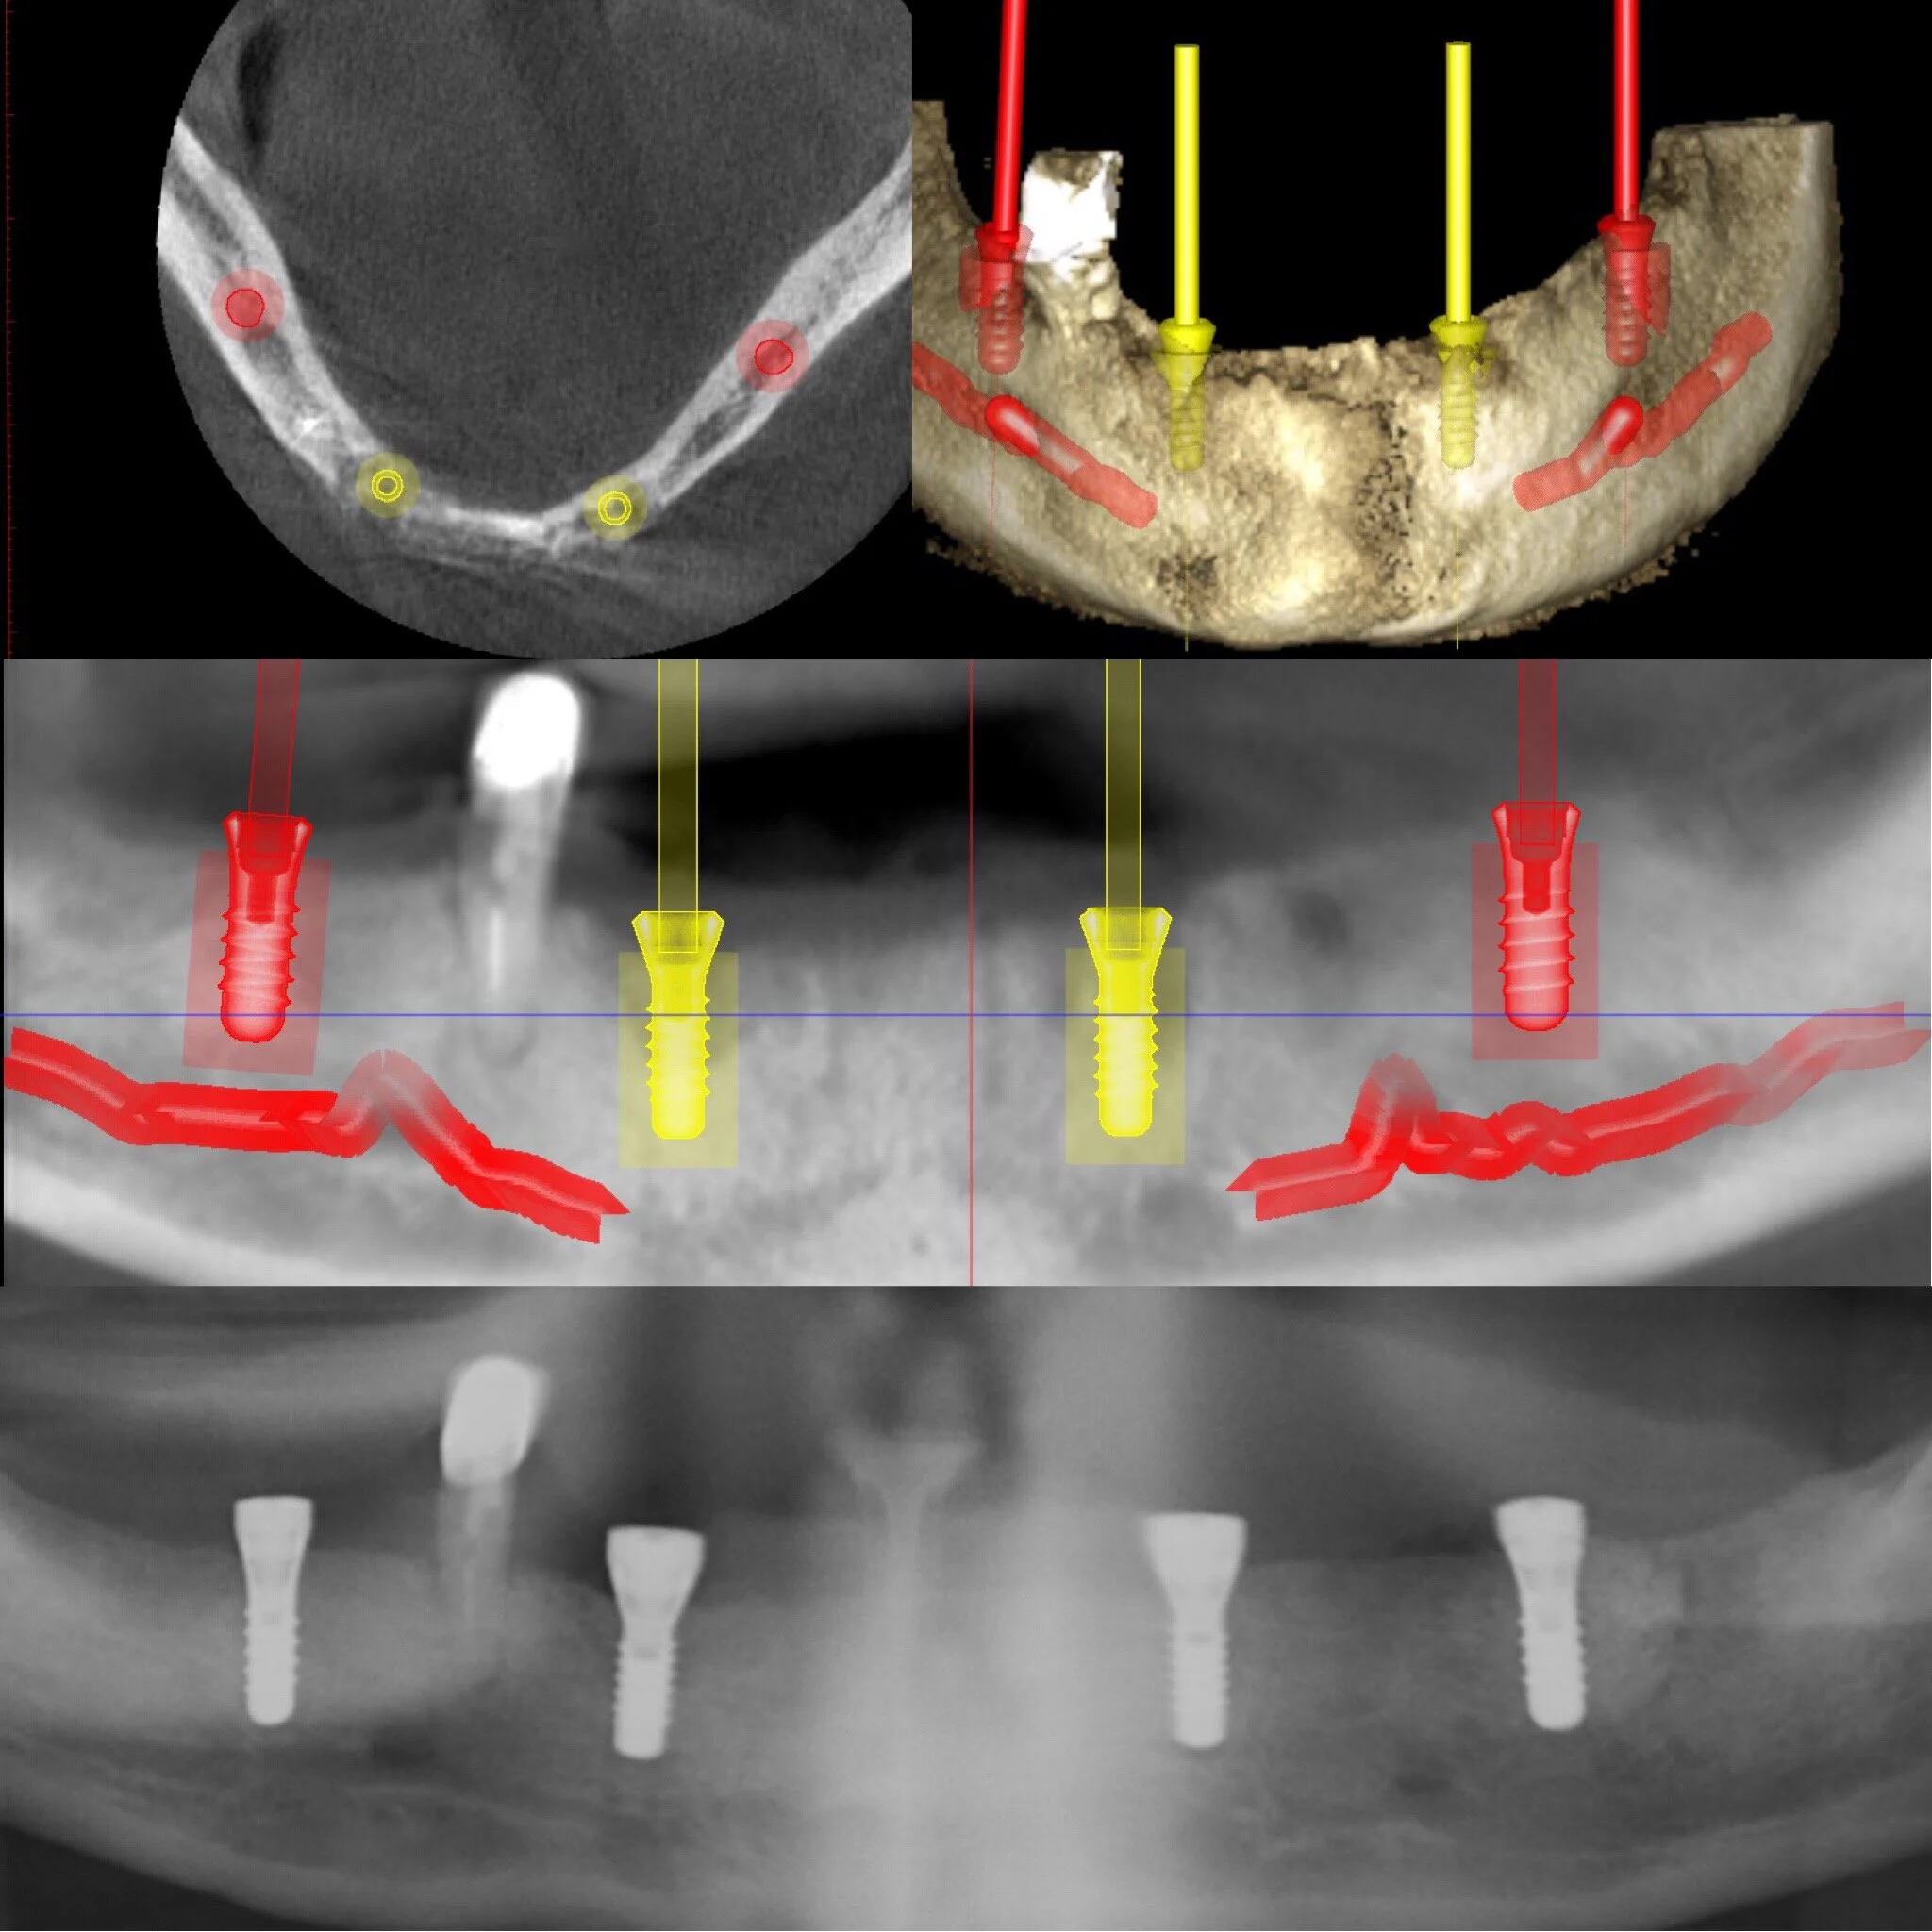

Utredningen kommer sedan att stå som en biologisk grund för Din behandling där faktorer som allmänhälsa, oral hälsa, mediciner, mjukvävnad m.m kommer att studeras. Benvolym utvärdeas med hjälp av avancerad röntgenteknik som avbildar käkarna i 3D. Bilden förs sedan över till ett datorprogram där Dr. Osama planerar behandlingen utifrån Dina förutsättningar. På så sätt kan implantaten placeras med mycket hög precision och kvalitet. Detta för att ge Dig ett resultat som både är biologiskt, funktionellt och anpassat efter just Dina förväntningar/önskemål.